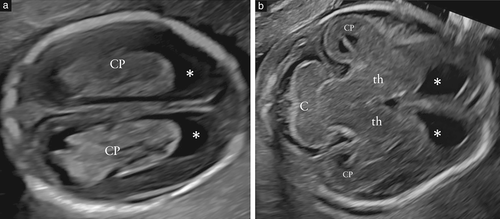

胎儿超声检在早孕期最后几周和中孕早期越来越多,这些检查包括对大脑的评估,但是到目前为止,还没有关于这些检查临床指南。我们认为,每次胎儿脑部检查均应至少包括脑室和小脑平面的观察图6)。由于在怀孕期间和分娩后都会发生大脑的快速动态发育变化,不仅要告知患者这些检查的技术局限性,还应告知患者与时间问题有关的技术局限性。

图6 16周时胎儿大脑的脑室平面(a)和小脑平面(b)。

(a)在脑室平面中,相对于周围的薄脑实质,侧脑室较大。额角(

*)是圆形的,充满了脑脊液。 脉络丛(CP)充满侧脑室的体,前、枕骨和颞角,并可能呈现不规则的外部边界。(b)在小脑平面中,在孕中期早期,小脑(C)呈哑铃状,存在上蚓部,呈回声性(而在妊娠后期呈弱回声)。 观察到侧前角(*)、丘脑(th),侧脑室的部分枕角及脉络丛(CP)。